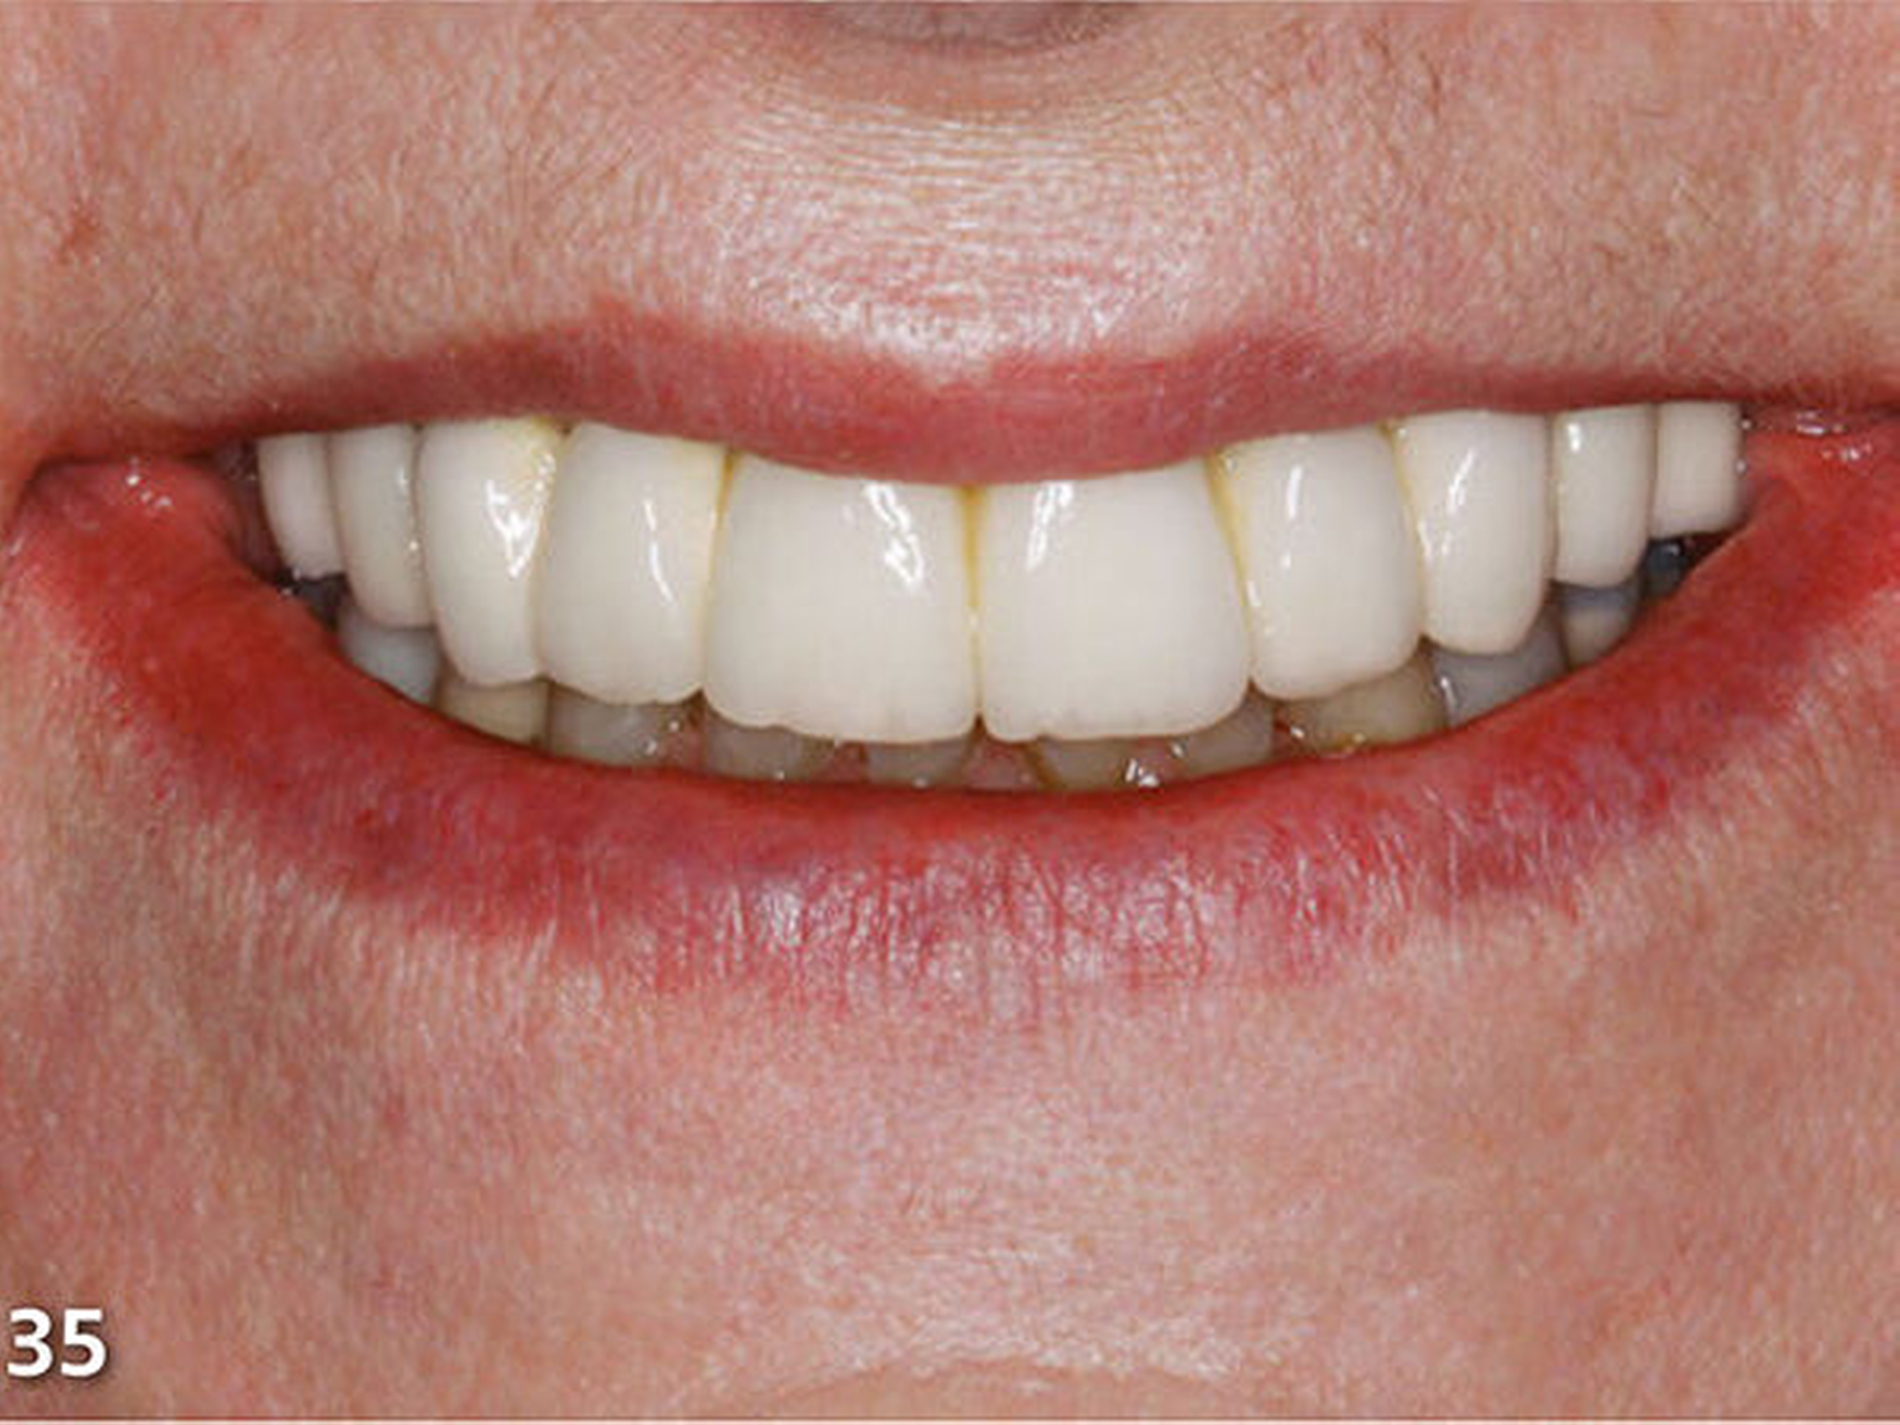

Nach dem Ausarbeiten und Polieren sämtlicher Restaurationen (Abb.31 und 32) wurden die statische und die dynamische Okklusion nochmals kontrolliert; es zeigte sich eine gute Übereinstimmung mit dem okklusalen Kontaktmuster aus dem Wax-up (Abb.33). Da sämtliche Restaurationen ohne Verabreichung von Lokalanästhesie aufgebaut wurden, konnte die Patientin sofort nach Abschluss der Behandlung, nach einer kurzen Phase der Lockerung der Kaumuskulatur, ein erstes positives Feedback zur neuen Unterkieferposition geben (Abb.34 und 35).